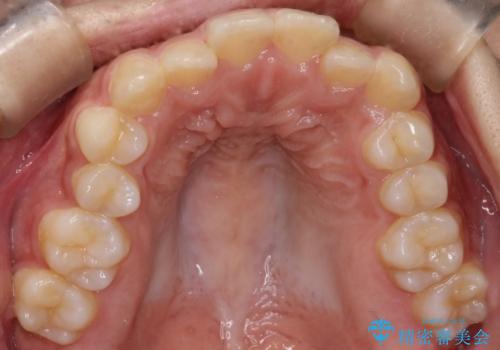

インビザライン 前歯のがたつきを目立たず矯正

- 前歯のがたつきが気になるとのことで来院されました。

インビザラインにて治療を行いました。

わずかに歯と歯の間に隙間を作り、歯列矯正を行いました。

マウスピースをしっかりと使用していただけたので、スムーズに治療を終了することができました。